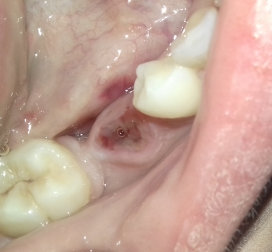

Мне 27 лет. Неделю назад лечила периодонтит 5-ого и 6-ого зубов. Через 4 дня 6-й зуб разболелся. И врач объяснила, что по снимку начался воспалительный процесс. В этом зубе была киста. Этот зуб удалили. Через день появилось уплотнение на щеке. Рана сама не беспокоит. Болей сильных нет.

Что это может быть? Может это от частых анестезий травмируется слизистая?

После удаления зуба отек щеки - это норма. Главное, чтобы он не сопровождался увеличением, болью и нарастанием, повышением температуры тела, яркой гиперемией слизистой. В случае ухудшения состояния обратитесь к хирургу.